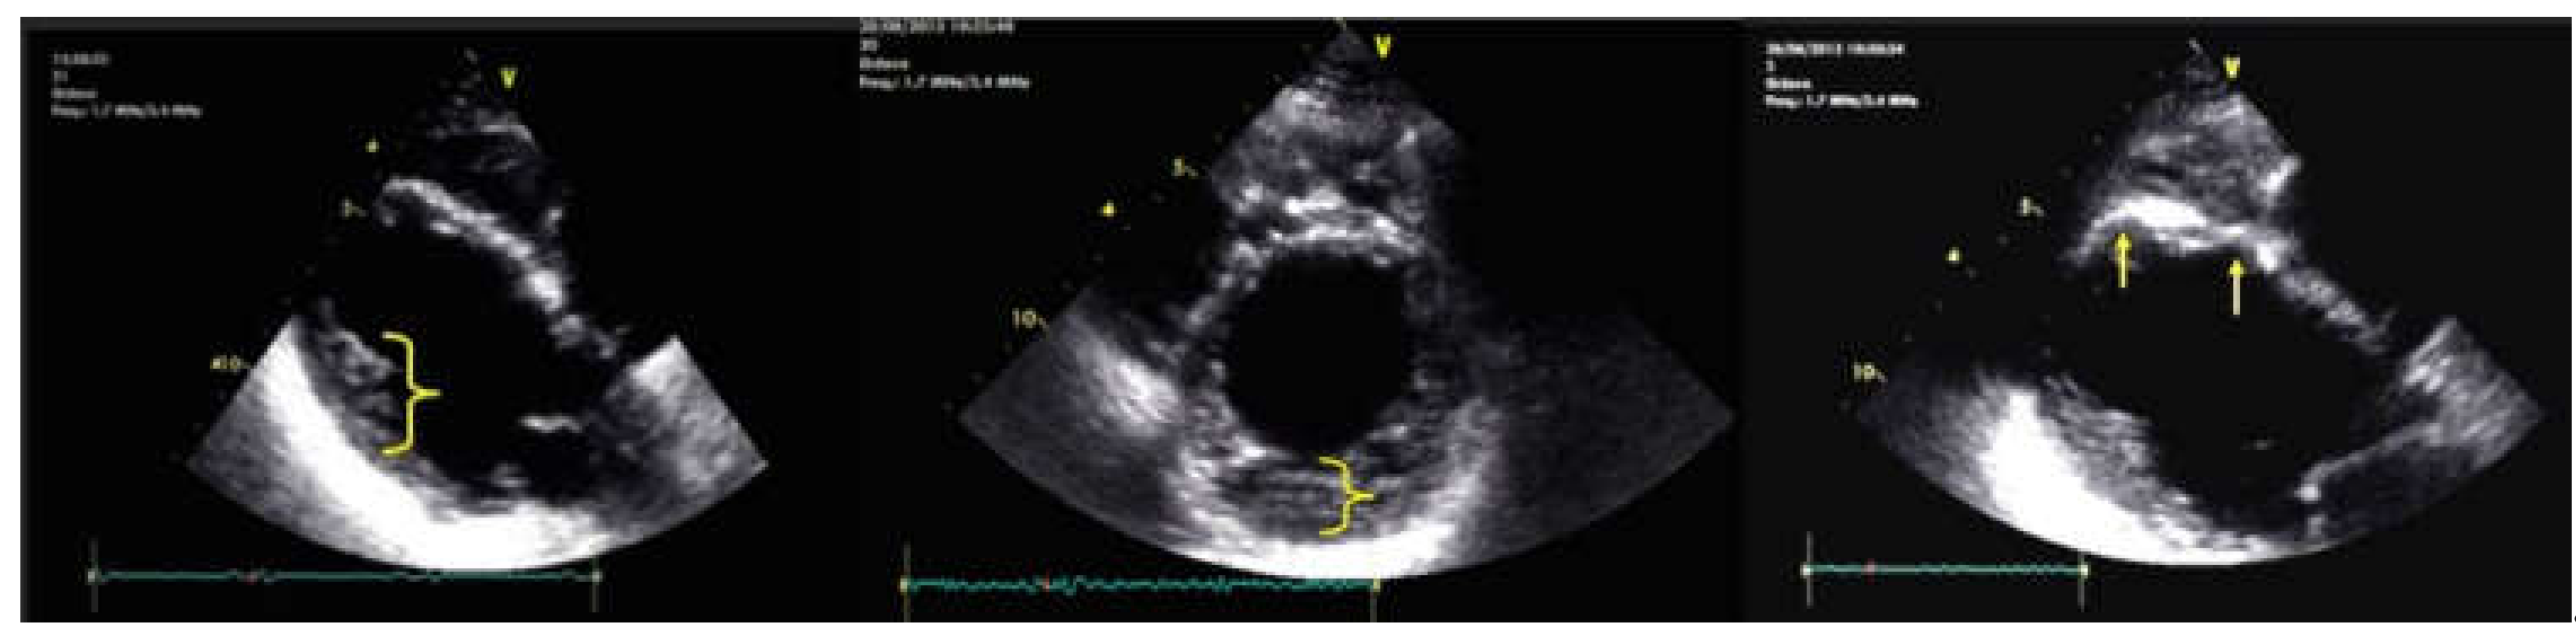

5. Cases Presentation